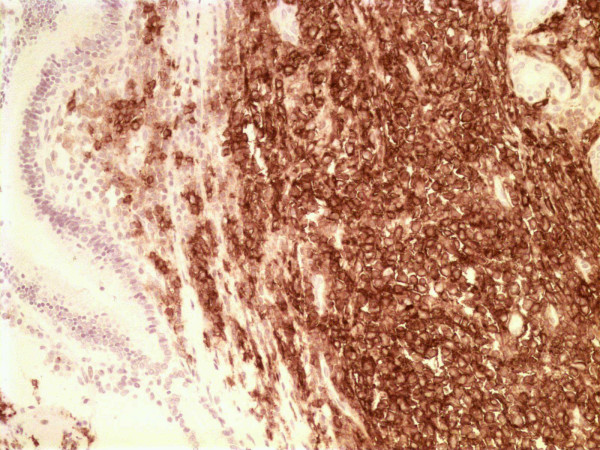

Figure 3.

CD20 positivity of neoplastic lymphoid cells (CD20 × 200).